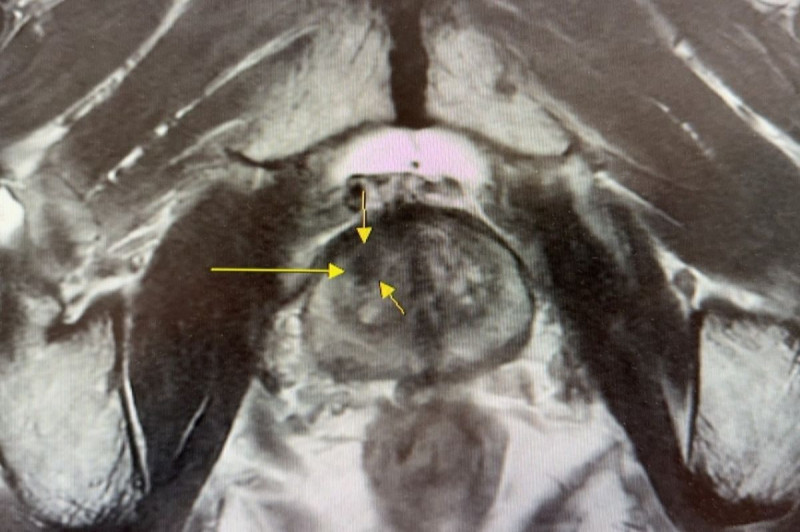

台北慈濟醫院指出,在早期診斷方面,院方以「核磁造影與超音波影像融合攝護腺切片」,取代傳統「經直腸超音波攝護腺切片」,利用3D影像融合技術將核磁造影顯示的病灶與超音波重疊,避免誤判良性或需要重複切片的情形發生。這樣的改變,讓切片準確率提升6至7成;末期患者治療中,第4期的5年存活率則達近6成,整體成效高於全國醫學中心。